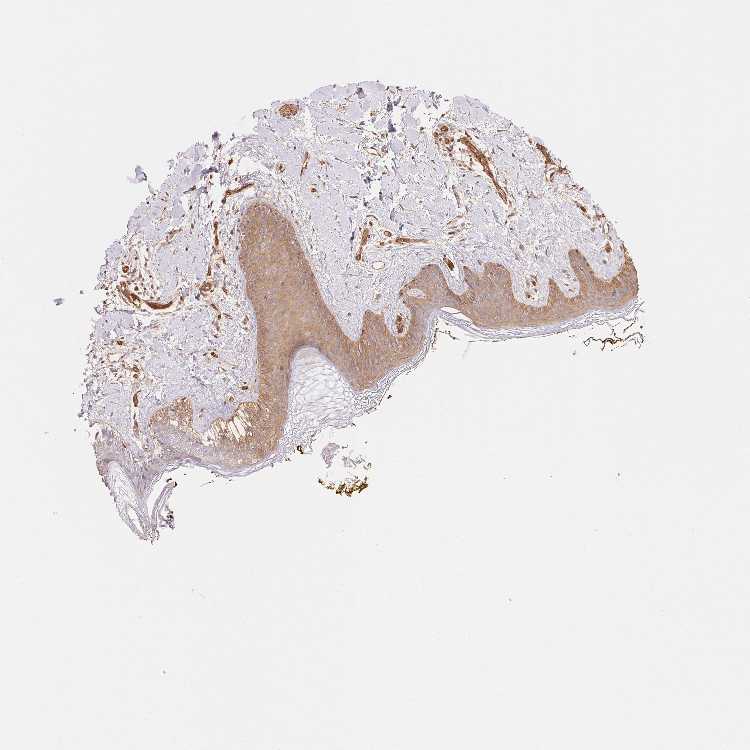

SKIN 1 - Antibody stainingi

Antibody staining in the annotated cell types in the current human tissue is reported as not detected, low, medium, or high, based on conventional immunohistochemistry profiling in selected tissues. This score is based on the combination of the staining intensity and fraction of stained cells.

Each image is clickable and will lead to virtual microscopy that enables deeper exploration of all samples and also displays staining intensity scores, fraction scores and subcellular localization as well as patient and tissue information for each sample.

Antibody HPA051601

Langerhans High

Fibroblasts Medium

Keratinocytes Medium

Melanocytes Medium